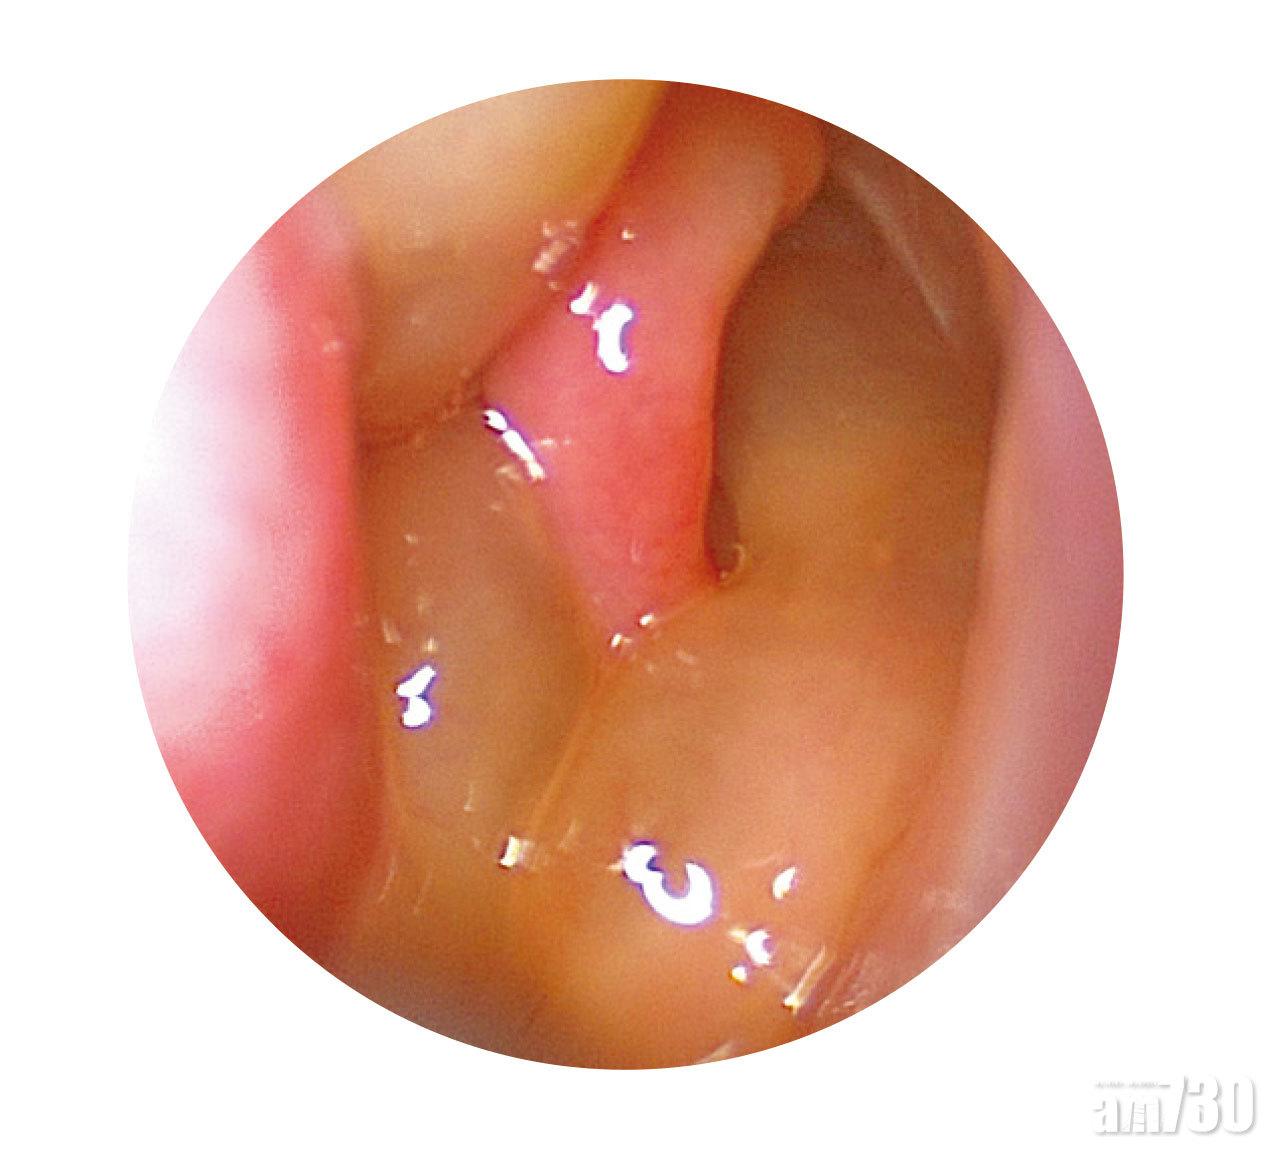

內窺鏡作診斷

透過內窺鏡可輕易診斷病情,一旦發現兩邊鼻息肉,可使用類固醇、生理鹽水、抗敏感藥治療,若有鼻竇炎便要加入抗生素。當病人覺得息肉太大阻礙呼吸,便可考慮做內窺鏡微創手術切除,除了徹底把鼻息肉切除外,還會切除受阻塞的鼻竇。不過,若發現只有單邊出現息肉,便要擔心會否屬於腫瘤,建議抽取組織作進一步化驗。